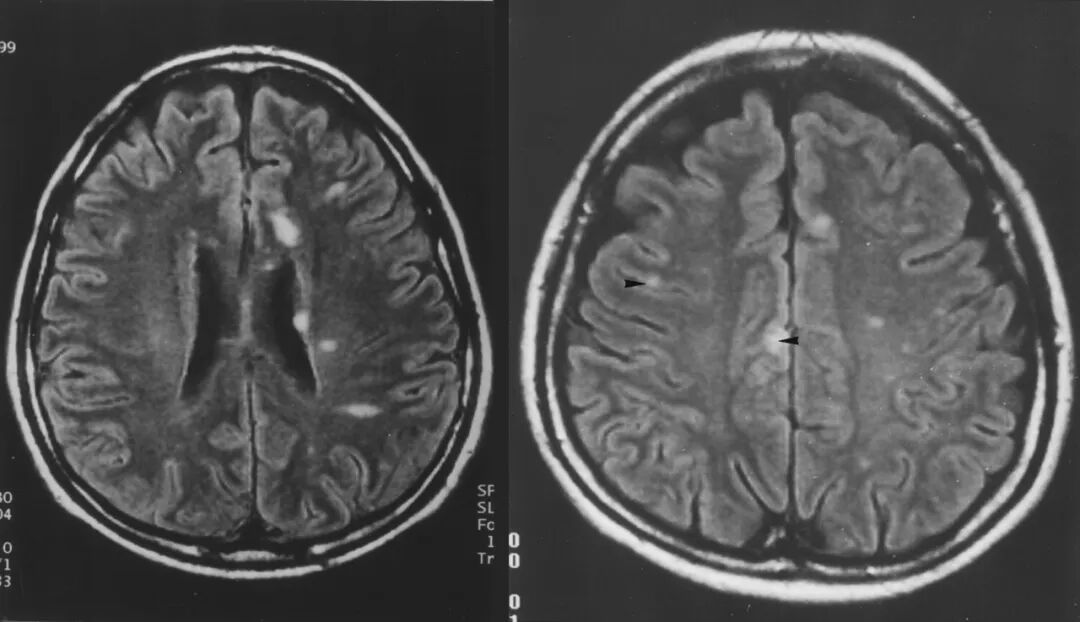

尼帕脑炎患者的脑部病灶(白色部分)

(图:ajronline.org)▼

即便幸运地活了下来,仍有相当比例的幸存者在康复后出现癫痫等长期神经系统后遗症。世界卫生的调查报告,以及多项随访研究都明确提到,尼帕病毒感染的“远期神经损伤”问题不容忽视。